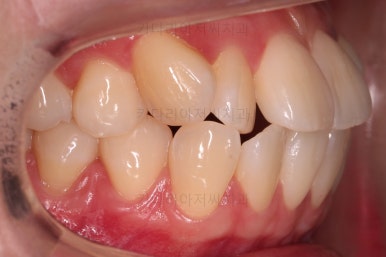

마찬가지로 초진 시 입안의 모습인데요.

전반적으로 약간 삐뚤지만 특히 윗니 앞니가 삐뚤고요.

송곳니는 덧니처럼 튀어나와 보이네요.

그리고 전반적으로 치아가 앞쪽으로 경사되어 있어서 앞니는 뻗친 느낌이 있네요.